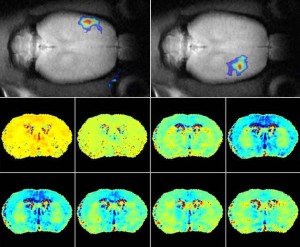

I risultati innanzitutto confermano quanto già è noto da tempo ai ricercatori: raffreddare il cervello significa proteggere i neuroni e ridurre il danno che provoca l’ictus. Dopo 24 ore infatti il tessuto cerebrale dei topolini “raffreddati” era più conservato e i neuroni mostravano meno segni di lesioni. A un gruppo di animali i ricercatori hanno somministrato l’attivatore tissutale del plasminogeno, ovvero il farmaco che viene utilizzato anche nell’uomo per sciogliere i trombi: dandolo senza precauzioni, 90 minuti dopo aver indotto l’ictus, purtroppo induceva anch’esso qualche danno. Succede perché di fatto riaprire i vasi occlusi è come aprire una diga: il flusso di sangue irrompe in arterie indebolite dalla mancanza di ossigeno durante l’ictus e questo può lesionarle.

MENO DANNI – La sorpresa è che, almeno nei topolini, mantenere freddo il cervello diminuendo prima possibile la temperatura corporea significa ridurre anche questi effetti collaterali da terapia trombolitica. «Sappiamo che anche nell’uomo la terapia deve essere somministrata entro le prime ore da un ictus per avere effetto e perché i vantaggi siano maggiori degli effetti collaterali: se si aspetta troppo prevale lo “shock” che si ha quando si riapre la circolazione e sono più probabili un edema cerebrale ed emorragie intracerebrali – spiega Rainer Kollmar dell’università di Erlangen, coordinatore della ricerca –. I nostri dati mostrano che raffreddare il corpo e quindi il cervello diminuisce la probabilità di effetti collaterali da terapia: anche i marcatori di infiammazione e di lesioni alla barriera emato-encefalica che protegge il cervello dal resto dell’organismo sono diminuiti. Questo implica che un intervento semplice e a basso costo, eseguibile anche sul paziente sveglio e cosciente, può avere ottimi risultati: l’ipotermia può infatti allungare la “finestra” temporale durante la quale è possibile somministrare la terapia trombolitica godendo dei massimi vantaggi e dei minori effetti collaterali». E che sul “gelo” per bloccare l’ictus puntino in molti lo dimostra il fatto che l’Unione Europea ha da poco stanziato 11 milioni di euro per finanziare uno studio clinico che sta coinvolgendo 60 università di 25 Paesi, proprio per trattare con l’ipotermia 1500 vittime di ictus e verificarne una volta per tutte l’efficacia.